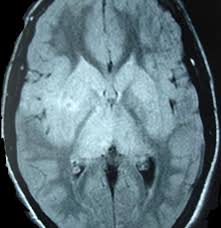

Two subtypes are recognised which differ in demographics, virus, and pattern of involvement. Mri demonstrates extensive edema in the right temporal lobe with areas of intrinsic high t1 signal, in keeping with hemorrhage. Terminology the entity or closely related variants have also been. Coccidioidal meningitis refers to central nervous system involvement of the dimorphic fungus coccidioides spp, mainly coccidioides immitis and coccidioides posadasi. Note the high signal in the caudate heads and putamen on flair.

Pcr was repeated on the biopsy specimen and was positive for hsv. Limbic encephalitis, mca ischaemia, tumours, effects of seizures) hyperintense t2 signal in the medial temporal lobes, inferior frontal lobes and insula basal ganglia are usually spared Axial t2 prominent swelling, increase t2 signal involving the left temporal lobe and insular cortex. Multilocularis, and describes a spectrum of disease involving the spinal cord, the spine, or both. Mri is the diagnostic modality of choice abnormal in 90%; A brain biopsy was performed and the histology was consistent with encephalitis. Mri demonstrates extensive edema in the right temporal lobe with areas of intrinsic high t1 signal, in keeping with hemorrhage. For a general discussion, and for links to other system specific manifestations, please refer to the article on hydatid disease.

The basal ganglia are usually spared. Mri is the diagnostic modality of choice abnormal in 90%; Hsv encephalitis | radiology case | radiopaedia.org. Axial t2 prominent swelling, increase t2 signal involving the left temporal lobe and insular cortex. For a general discussion, and for links to other system specific manifestations, please refer to the article on hydatid disease. Herpes simplex (hsv) encephalitis is the most common cause of fatal sporadic fulminant necrotizing viral encephalitis and has characteristic imaging findings. Herpes simplex virus (hsv) is a human herpesvirus that causes hsv encephalitis (hse), which is the commonest fatal sporadic encephalitis in humans. Hse may result from primary infection or reactivation from latency, and it frequently involves frontal or temporal lobes, as well as the brain stem. The differential diagnoses include limbic encephalitis (paraneoplastic), gliomatosis cerebri, and status epilepticus. A brain biopsy was performed and the histology was consistent with encephalitis. For a general discussion, and for links to other system specific manifestations, please refer to the article on hydatid disease. Cerebral malaria is a rare intracranial complication of a malarial infection. Bilateral temporal lobe t2 hyperintensity refers to hyperintense signal involving the temporal lobes on t2 weighted and flair imaging.

The differential diagnoses include limbic encephalitis (paraneoplastic), gliomatosis cerebri, and status epilepticus. Ventriculitides) refers to inflammation, usually due to infection, of the ependymal lining of the cerebral ventricles. For a general discussion, and for links to other system specific manifestations, please refer to the article on coccidioidomycosis. Herpes simplex (hsv) encephalitis is the most common cause of fatal sporadic fulminant necrotising viral encephalitis and has characteristic imaging findings. Bilateral temporal lobe t2 hyperintensity refers to hyperintense signal involving the temporal lobes on t2 weighted and flair imaging. For a general discussion, and for links to other system specific manifestations, please refer to the article on hydatid disease. Given the history of fever and seizures coupled with the mri findings of bilateral mesial temporal lobe changes, herpes encephalitis requires clinical consideration. It is most often due to meningitis. Multilocularis.the larval stage is the cause of hydatid disease in humans 1. Spinal hydatid disease is an uncommon manifestation of hydatid disease, caused by the larval stage of echinococcus granulosus, or less commonly e. Terminology cerebritis is essentially the same as encephalitis except that it is used to denote brain par. It is a common finding on brain mri and a wide range of differentials should be considered 1. It is usually bilateral but asymmetrical.

The changes spare the basal ganglia, a feature which is helpful in distinguishing an mca infarct with hemorrhagic transformation from herpes simplex encephalitis, the diagnosis in this case. Hse may result from primary infection or reactivation from latency, and it frequently involves frontal or temporal lobes, as well as the brain stem. Herpes simplex (hsv) encephalitis is the most common cause of fatal sporadic fulminant necrotizing viral encephalitis and has characteristic imaging findings. It is usually bilateral but asymmetrical. The differential diagnoses include limbic encephalitis (paraneoplastic), gliomatosis cerebri, and status epilepticus. Two subtypes are recognized which differ in demographics, virus, and pattern of involvement. Given the history of fever and seizures coupled with the mri findings of bilateral mesial temporal lobe changes, herpes encephalitis requires clinical consideration. Spinal hydatid disease is an uncommon manifestation of hydatid disease, caused by the larval stage of echinococcus granulosus, or less commonly e. Multilocularis.the larval stage is the cause of hydatid disease in humans 1. The differential diagnoses include limbic encephalitis (paraneoplastic), gliomatosis cerebri, and status epilepticus. Herpes simplex encephalitis (hse) is the most common form of viral sporadic encephalitis and, when left untreated, has a mortality rate of 70% (3, 22). This patient went on to have hsv encephalitis proven on csf pcr. Bilateral temporal lobe t2 hyperintensity refers to hyperintense signal involving the temporal lobes on t2 weighted and flair imaging.